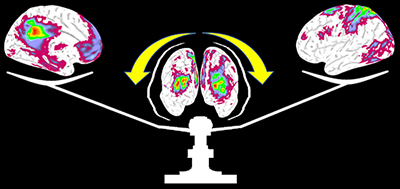

Recently, the notion that the brain operates on large-scale functional networks with dynamic interactions during different brain states has been increasingly accepted. Better understanding of such network-level dynamics in matured human brains will not only improve our understanding of the adult brain functioning mechanisms but also help the delineation of abnormal mechanisms in different brain disorders/diseases. The Gao Lab has documented, in normal adults, a potential regulating role of the frontoparietal control network between the anti-correlated default-mode and dorsal attention networks, the differential interaction mechanisms between the salience and executive control networks under task perturbations, the dynamic reorganization of the default-mode network across different behavioral states, and the task-modulation of functional connectivity variability.

Frontal parietal control network regulates the anti-correlated default-mode and dorsal attention networks to facilitate the switching between contrasting behaviors in normal adults. |